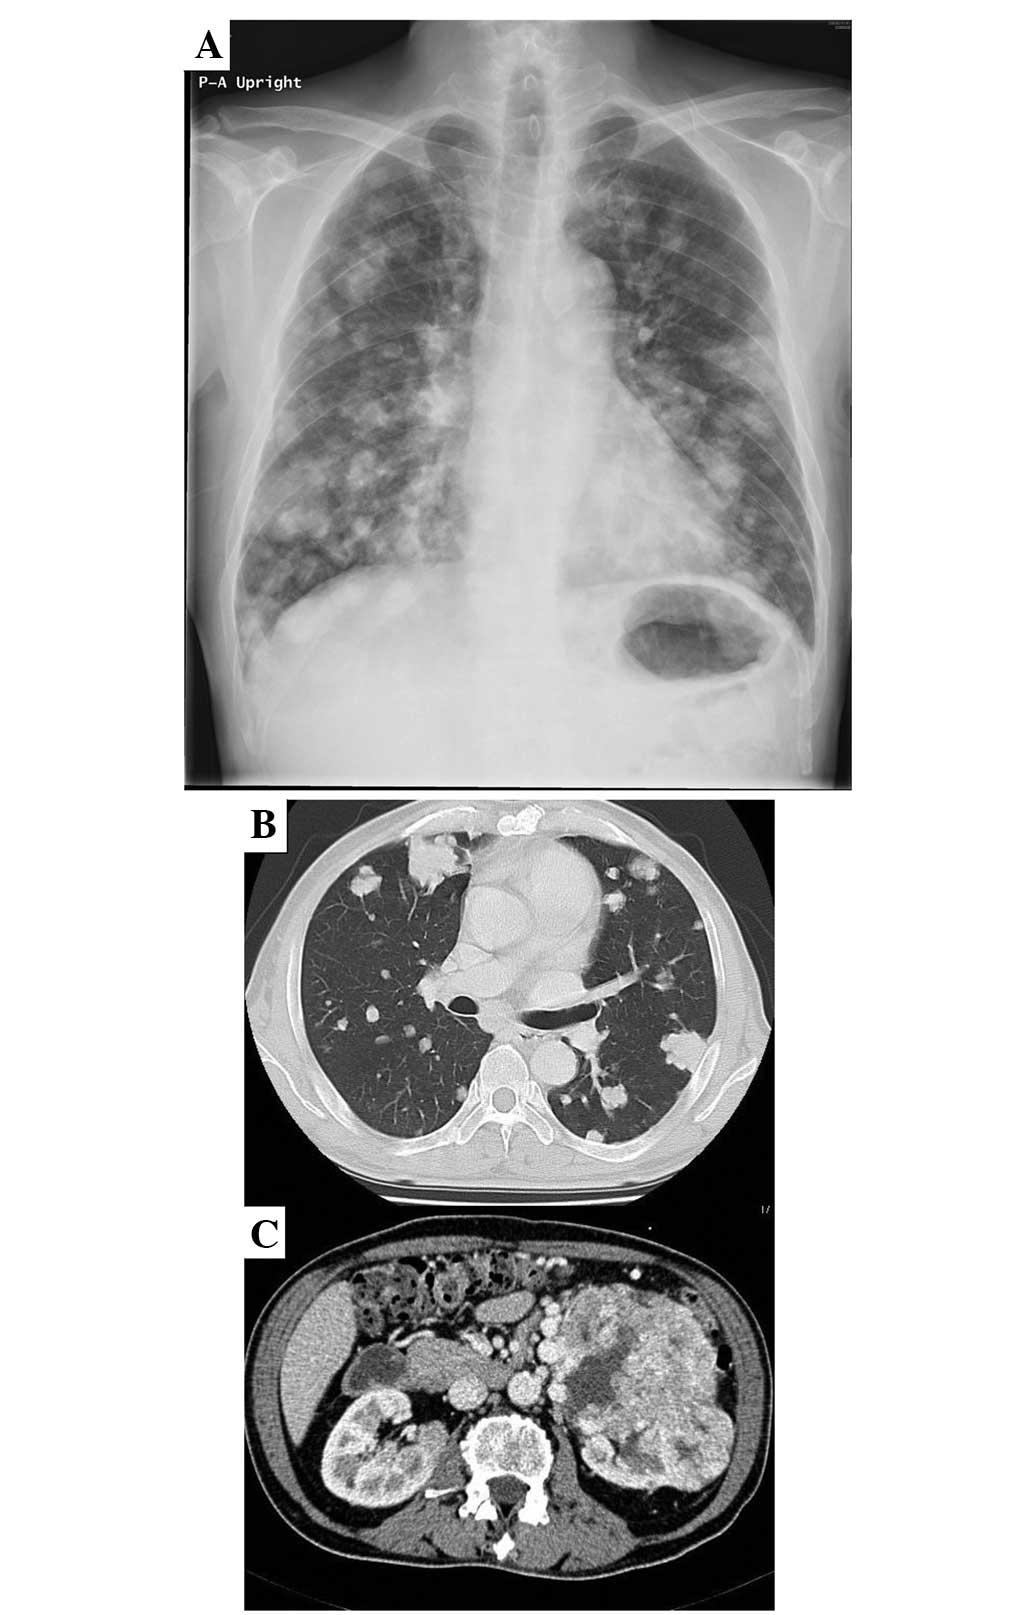

Case report demonstrating effectiveness of sorafenib in multiple lung and bone metastases of renal cell carcinoma

The current study presents the case of a 59‑year‑old male with advanced‑stage renal cell carcinoma and bone metastases in the proximal femur and ilium (cT3aN3M1; stage IV). Resection of the primary renal cell cancer and palliative surgery with a γ‑nail for an impending fracture of the right proximal femur were performed, followed by radiotherapy. Sorafenib, a multi‑kinase inhibitor that blocks the raf and tyrosine kinases of the vascular endothelial and platelet‑derived growth factor receptors, was administered for 9 months, resulting in a marked improvement in the metastatic ilium and a reduction in the extent of the lung metastases. The patient suffered minor adverse effects, including a skin rash and mild diarrhea, but remained alive at the time of follow‑up at 36 months post‑surgery. Sorafenib demonstrated efficacy against the bone metastasis of metastatic renal cell carcinoma.

Figure 1

Figure 2

Figure 3

Figure 4